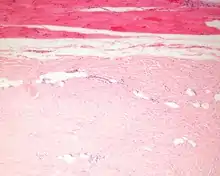

The tumors are unencapsulated and poorly circumscribed, showing a firm, white cut surface. Most tumors are about 3.5 cm, but can be up to 8 cm.[1] By microscopic examination, there are haphazardly arranged thick collagen fibers, with a low cellularity and no pleomorphism. There are usually entrapped fat cells, skeletal muscle, and peripheral nerves. The may be perineural fibrosis. The elastic fibers may be altered, which is why an elastofibroma is considered in the differential diagnosis.[1]